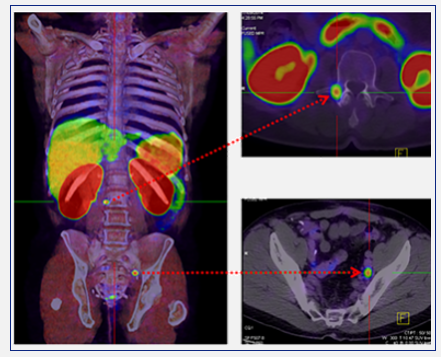

The PET-CT images ​